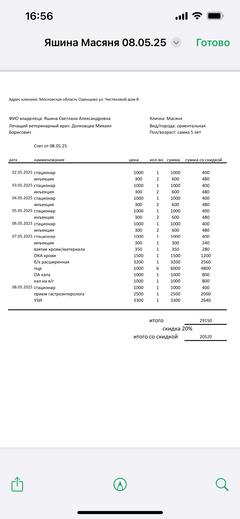

Была куплена в питомнике взрослой. У Масяни начались проблемы с кишечником и она стала подтекать и все пачкать. Надо отдать должное хозяевам - ее обследовали вдоль и поперек - как говорили местные врачи, сдавали много анализов но диагноза так и не поставили.

Ярко выраженная болезненность в области крестца, на обезболе полегче. По результатам приема невролога проведена миелография - множественная компрессия, возможно опухоль, возможно грыжа, нужно удалять...